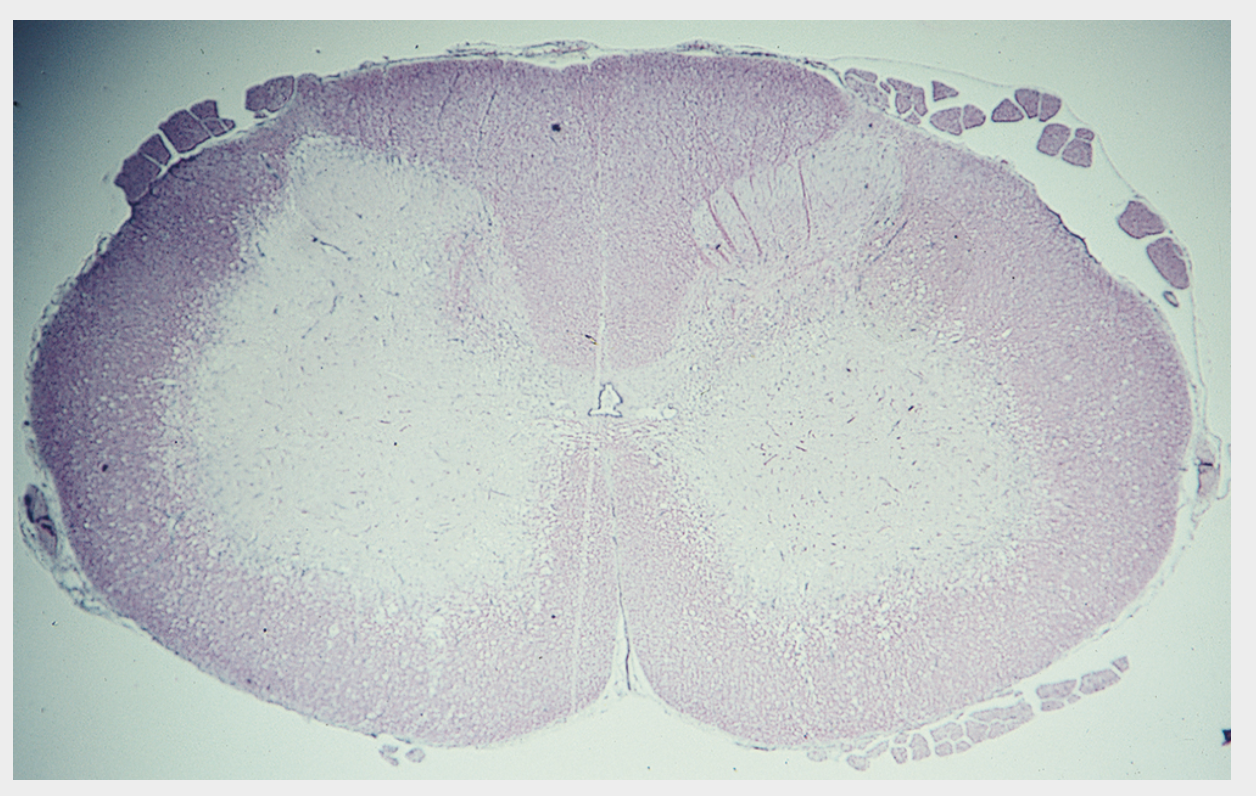

Q

See image, most likely dx? SC of a pig

Selenium poisoning (poliomyelomalacia) There is bilaterally symmetrical loss of staining in the ventral horns of the cervical intumescence due to poliomyelomalacia. Microscopically, initial lesions include neuropil vacuolation, necrosis of glial cells, capillary hypertrophy and neuronal degeneration. In the chronic stage, the picture is predominated by neuronal loss and extensive gliosis with capillary proliferation in the ventral horns. In addition, many brainstem nuclei and cerebellar roof nuclei may be similarly affected.